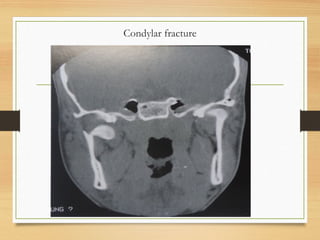

Condylar fracture

• The only maxillofacial fracture involving a

synovial joint

• Advent of CT and MRI has shown that

incidence is higher than previously

reported

• Multiple classification schemes